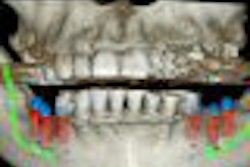

Researchers from the University of Bern compared cone-beam CT to conventional periapical radiographs in evaluating 38 mandibular molars with 75 roots prior to apical surgery. They looked at the detectability and dimensions of periapical lesions, the relationship of the mandibular canal to the roots of the respective teeth, and the dimension of the buccal bone.

Of 58 detected periapical lesions, 15 (25.9%) lesions diagnosed with sagittal cone-beam CT slices were missed with periapical radiography, the researchers found. The distance between the apices and the upper border of the mandibular canal was only measurable in 24 of 68 radiographs (35.3%) by using periapical images. The cortical bone wall had a mean thickness of 1.7 mm, whereas the total buccal bone wall measured 5.3 mm on average.